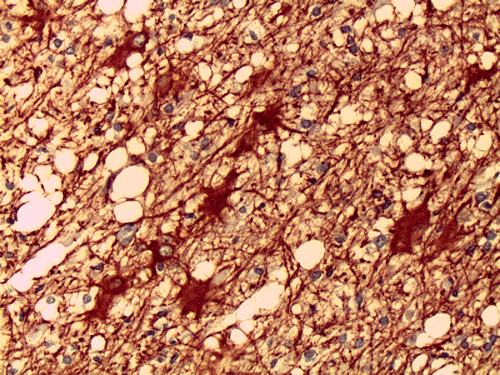

On CT scan, there is multiple hypodense white matter lesions that appear to spare a thin layer of subventricular white matter (Panel A). The T2-weighted images on MRI provides a more accurate estimation. The white matter in the occipital lobes is most affected (Panel A). There is extensive vacuolar changes in the white matter (Panel B and C) and there is a questionable increase in cellularity. In some of the thin walled blood vessels, there is a thin layer of perivascular lymphocytic infiltration which is free of atypia (Panel D, E, and F). The lymphocytes do not appear to extends into the parenchyma. On higher magnification, some large reactive astrocytes can be seen (Panel G). In a minority of areas, some concentric rings can be seen on hematoxylin-eosin stained sections (Panel H). These rings appear to be alternating rings of myelinated and demyelinated white matter and the vacuolar changes appear to be limited mainly to the concentric lesions. The adjacent myelinated areas are spared (Panel I). In some areas, the level of myelin loss appears to be proportional to the level of vacuolar changes (Panel J and K). On immunohistochemistry for glial fibrillary acidic protein (GFAP), the degree of gliosis is also more impressive in areas with more prominent vacuolar changes (Panel L and M). The vacuolar areas also appear to have a reduced density of axons (Panel N). Axonal spheroids are also present in these areas (Panel O). Although a prominent infiltration of foamy histiocytes is not noted on hematoxylin-eosin stains, immunohistochemistry for CD68 illustrated positive cells in a minority of demyelinated areas (Panel P). These cells lacks the foamy nature of macrophages and their morphology would suggest microglial cells. The reactive astrocytes are not immunoreactive for CD68 (Panel Q). Immunohistochemistry for T-cells (CD3) and B-cells (CD20) demonstrates only a thin rim of perivascular infiltration without significant extension into the surrounding parenchyma (Panel R, S, and T).

Pathology

On histology, there are extensive spongiform degeneration and vacuolar degeneration of the deep white matter associated with variable macrophage, profound axonal loss, degenerating axons with spheroid formation and evidence of axonal injury in adjacent normal appearing white matter  1, 2, 3, 4. Demyelinating changes featured by lost of myelin and infiltration of macrophages have also been described  1,  2, 5,  6. Under the electronic microscope, there are vacuolar degeneration of the oligodendroglia, swollen mitochondria and distended endoplasmic reticulum.